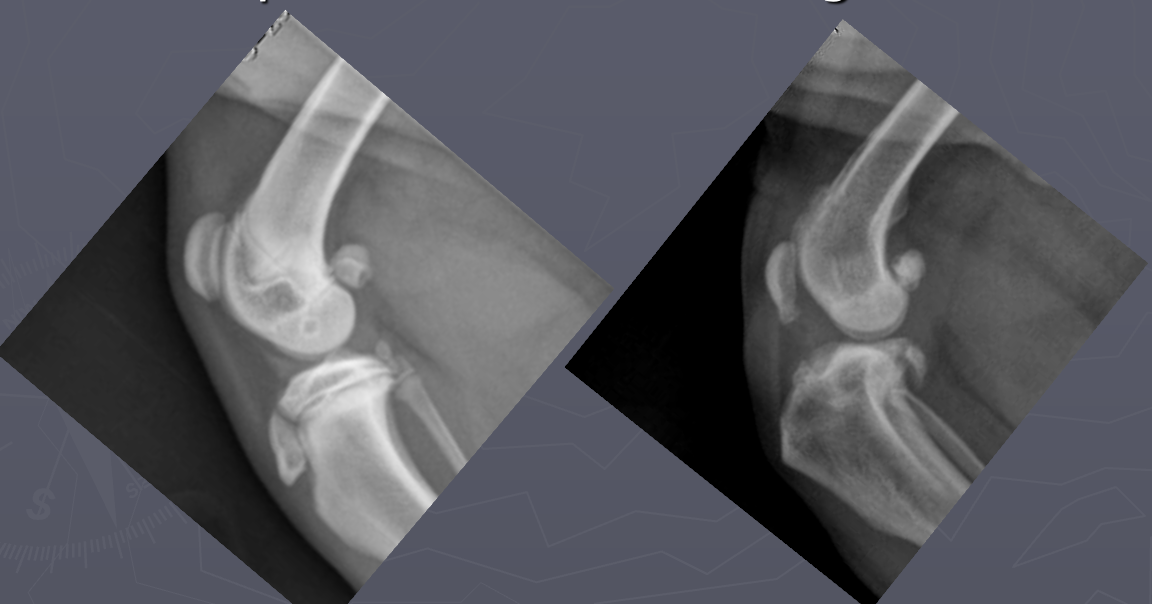

Which radiograph is normal and which is abnormal? Why?

A

Left: normal; infrapatellar fat pad is of normal size and placement

Right: abnormal; infrapatellar fat pad is displaced and compressed due to intracapsular swelling

Left: normal; deep fat caudal to the joint is in normal position

Right: abnormal; displacement of fascial planes caudal to joint due to intracapsular swelling; joint pouch buldges